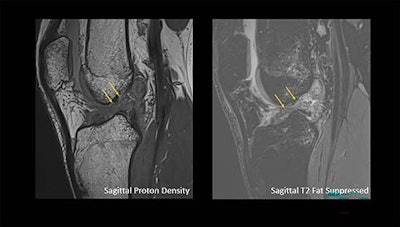

Arrows show a complete anterior cruciate ligament rupture in an 18-year-old male who had a knee injury while playing football.Arrows show a complete anterior cruciate ligament rupture in an 18-year-old male who had a knee injury while playing football.RSNAAccording to the analysis, there were more ACL tears alone, ACL tears with MM tears, and ACL tears with LM tears in men than in women, except in individuals over 60 years old. Meanwhile, men under 41 had more MM tears and LM tears alone than women, but women over 41 had more of these injuries, the researchers reported.